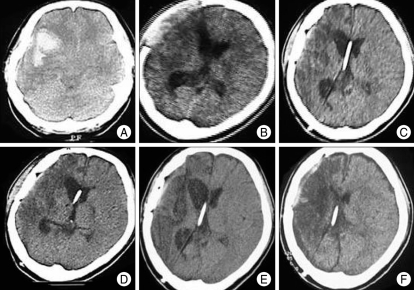

Case 2

A 35-year-old female patient with aneurysmal SAH underwent shunt surgery after aneurysmal neck-clipping and removal of ICH (Fig. 7A). The initial opening pressure was set at 140 mmH2O, because her lumbar tapping pressure was greater than 180 mmH2O (Fig. 7B). Her valve was adjusted 3 times, but there was no definite improvement in her condition (Fig. 7C). After the final valve adjustment from 50 to 30 mmH2O, she showed a marked improvement; several months later, she could walk with assistance (Fig. 7D, E). Twenty-six months after the shunt operation, her neurological status was the same, except for chronic postural headache. A slight subdural collection developed on follow-up CT scanning (Fig. 7F). The valve-opening pressure was increased from 30 to 50 mmH2O, and her headache improved.

A 35-year-old female patient with aneurysmal subarachnoid hemorrhage received shunt surgery after aneurysmal neck-clipping and removal of intracerebral hemorrhage. A : Computerized tomographic (CT) scanning shows aneurysmal subarachnoid hemorrhage and severe brain edema. B : CT scanning 25 days after craniectomy and aneurysmal neck-clipping showing ventricular dilatation and brain-bulging through the craniectomy area. C : CT scanning 2 weeks after the first adjustment of the valve-opening pressure to 100 mmH2O; there is persistent ventricular dilatation (initial valve-opening pressure was 140 mmH2O). D : CT scanning 64 days after the fourth adjustment of the valve-opening pressure to 30 mmH2O; there is a slight decrease in ventricular dilatation. After the final valve adjustment from 50 to 30 mmH2O, she showed marked improvement; several months later, she could walk with assistance. E : CT scanning 6 months after the final adjustment of the valve-opening pressure to 30 mmH2O; there is persistent mild ventricular dilatation. F : CT scanning 22 months after the final adjustment of the valve-opening pressure to 30 mmH2O; there is a mild late subdural collection and collapsed ventricle, and she complained of a chronic postural headache. The valve-opening pressure was increased from 30 mmH2O to 50 mmH2O, and her headache then improved.